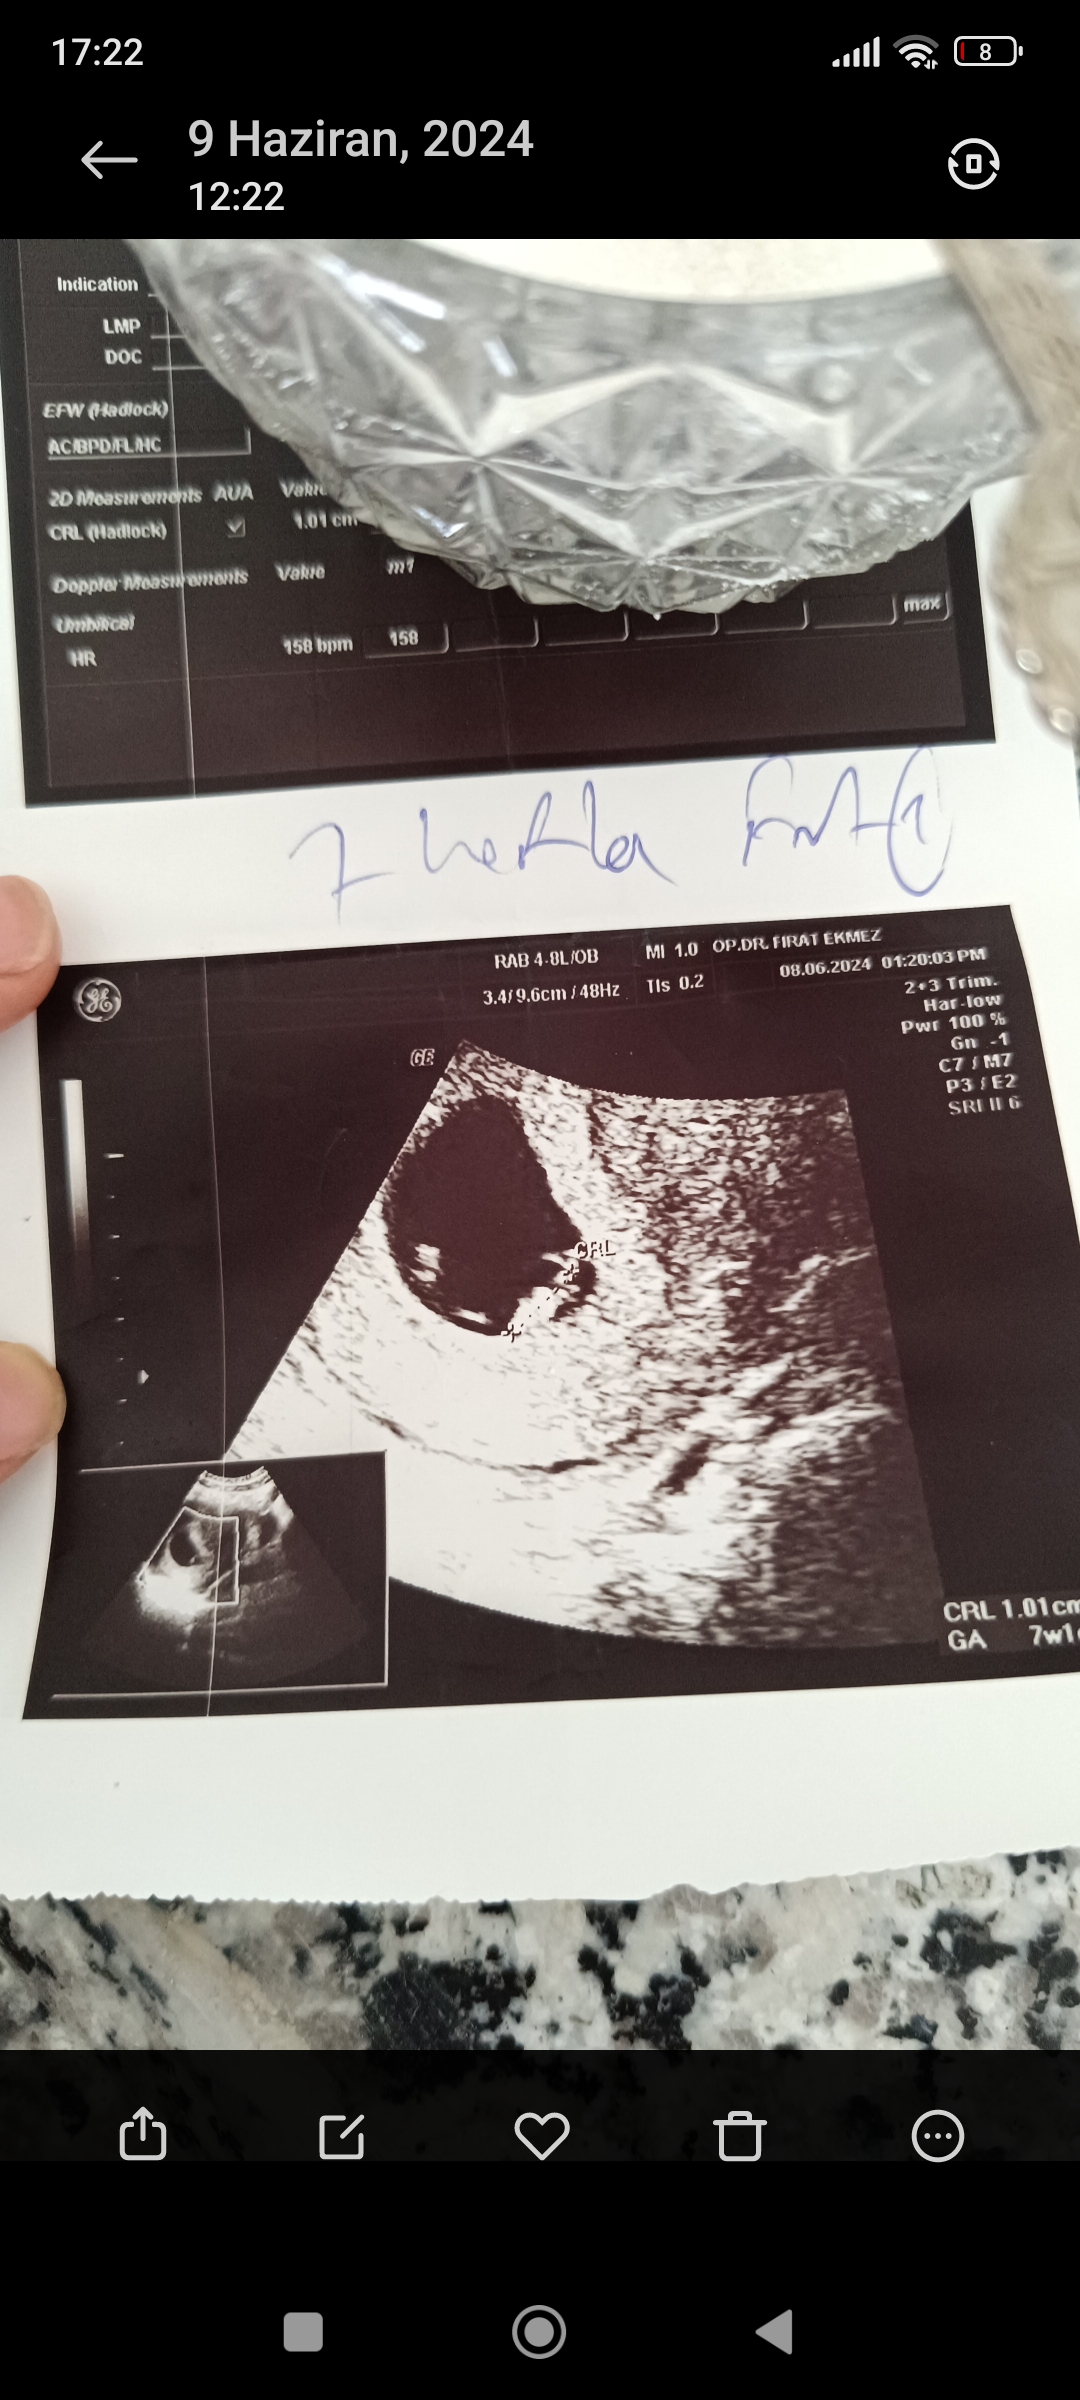

Ekli dosyayı görüntüle 5186

Buyrun tahminler bir kzizim var Allah'tan hep hayırlısını istiyorum merekta ediyor tabi insan c

Allahım miniick yarabbim 🥺😍. Rqbbim sağ Salim kucağına almayı nasip etsin inşallah canım kızın varmış birde oğluşun olur umarım sağlıklı bir şekilde